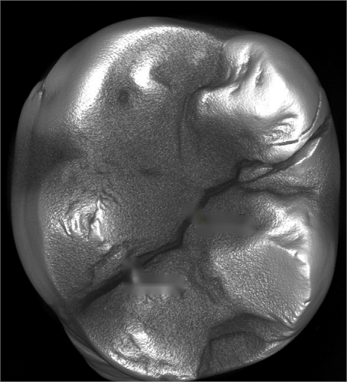

牙隱裂是指發(fā)生在牙冠表面的、不易被發(fā)現(xiàn)的細(xì)小裂紋,常不易被發(fā)現(xiàn)。這些裂紋可以深入到牙本質(zhì)結(jié)構(gòu),引起牙痛等一系列癥狀。牙隱裂具有隱匿性,診斷難,確診后療效不確定。

2. 口腔檢查時,醫(yī)生可能會使用探針、染色劑等工具輔助檢查,以確定裂紋的位置和深度。